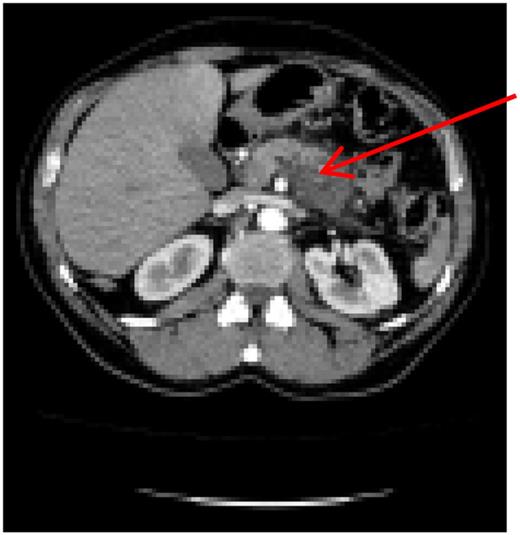

A 60-year-old male, with irrelevant medical history (no chronic disease or treatment), and complaining of recurrent abdominal pain, was referred for abdominal computed tomography (CT). Due to a suspicion of a mass in the pancreatic body (Fig. 1), the patient was referred to our hospital for re-evaluation and treatment. Physical examination was not remarkable, besides epigastric pain during deep palpation. All blood tests were within normal ranges. In re-evaluation of a previous CT, performed in a different hospital, our Radiological Department reported: ‘a malign appearing mass in the pancreatic corpus with extension to the pancreatic neck, with no invasion of the Superior Mesenteric Artery (SMA) and Superior Mesenteric Vein (SMV)’. Laparotomy was performed. Intraoperatively, a mass of ∼6–8 cm was discovered, located from the neck to the corpus of the pancreas. During exploration, the leading surgeon noticed that vascular structures, both the superior anterior pancreaticoduodenal artery (SAPDA) and the inferior anterior pancreaticoduodenal artery (IAPDA), which are collaterals between the gastroduodenal artery (GDA) and the SMA, were enlarged and tortuous. After the Kocher maneuver, all resections (jejunal, postpyloric gastric, common bile duct) were performed. Immediately after the GDA was clamped and cut, an ischemic appearance was seen on the liver and stomach. At this point, it came to mind that there was a total celiac trunk occlusion or possible MALS. To prevent ischemic hepatic injury, immediate re-anastomosis of the cut GDA was performed. After re-anastomosis was completed, a rapid change in the color of the liver and stomach was observed. And after re-anastomosis of the GDA, digital palpation and Doppler ultrasonography revealed that circulation of the common hepatic artery, splenic artery and left gastric artery was restored, and all these vascular circulations were from the SMA via the GDA.

Preoperative computer tomography, mass (arrow) located in corpus of the pancreas.